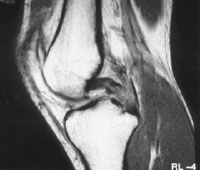

Figure 2: MRI scan showing complete tear of the posterior cruciate ligament

The diagnosis of PCL injury is usually made based on the description of the injury, your symptoms and a thorough visual and physical examination of the knee. The injured knee will be compared with the normal knee particularly assessing if there is any abnormal sag or movement of the tibia on the femur. An x-ray will be performed to exclude any bony injury and you will also require a MRI (see fig. 2) to assess the extent of the injury to other structures.